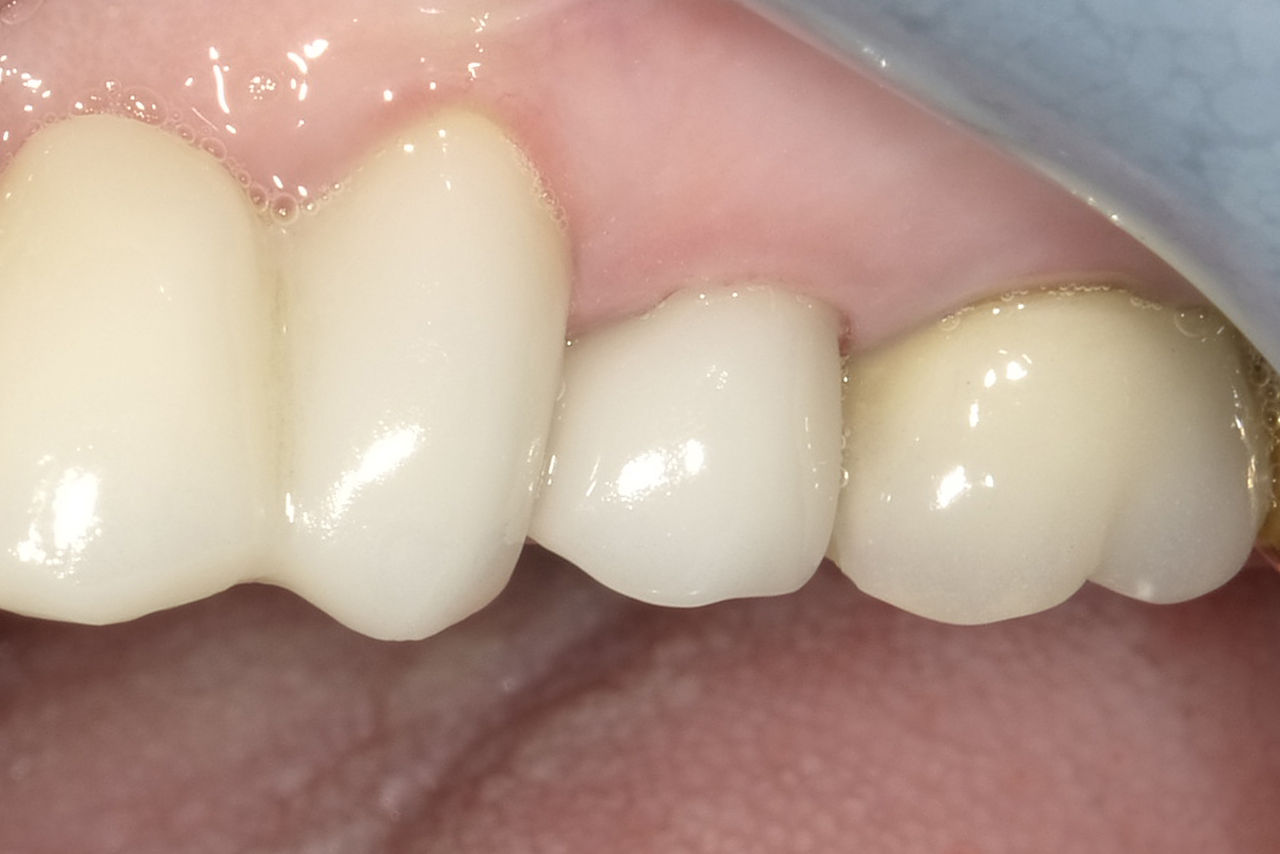

Upper central incisors, in 4 hours

Four IPS e.max CAD single crowns

The restoration with all-ceramic crowns did not require subgingival preparation to cover the margin and no dark metal shadows disturbed the aesthetics. With CEREC Primescan and CEREC Primemill patients receive a high-quality all-ceramic restoration faster than ever before.

Before: Inadequate fillings on teeth 12-22, an uneven gingival line on 12 and 11 and incisal edges severely eroded.

After: Four highly aesthetic and individualised lithium disilicate ceramic crowns.